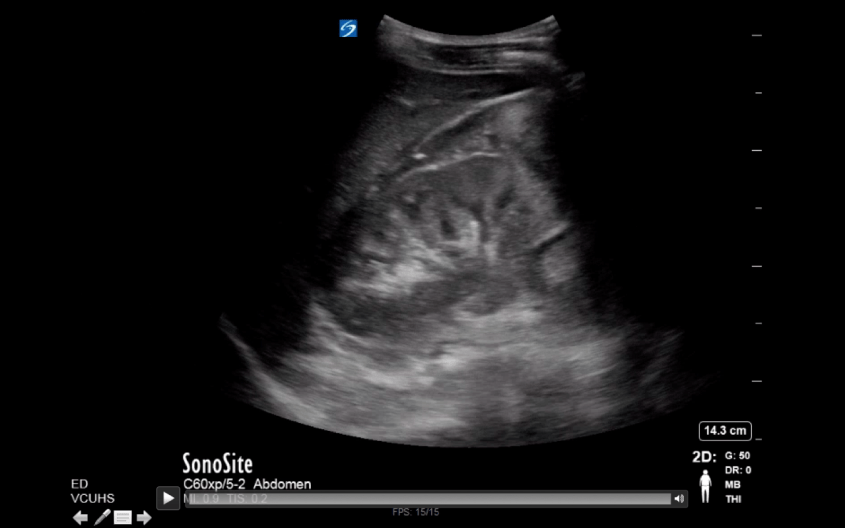

If you work in the medical field, you’ve likely had to present a patient case report. You do a chart review, gather the physical exam and lab data, but often importing the CT scans, ultrasounds, MRIs and other video imaging for display in your PowerPoint can be a time-consuming and frustrating task.

Step 1: Open up your Radiology imaging viewer and select the scan you wish to include.

Step 4: A tan box will appear, asking you either click once to record the full screen, or drag and select with your mouse the portion of your screen you want included in your screen capture. For capturing radiology images, you’ll want to make sure you include only the image and exclude any personal identifiers to be HIPAA compliant.

Step 5: While recording, scroll through your imaging study making sure to include everything you want to display. I recommend scrolling through by clicking the arrows on the keyboard rather than using the mouse, as the cursor may accidentally enter the image field and therefore appear in your presentation.